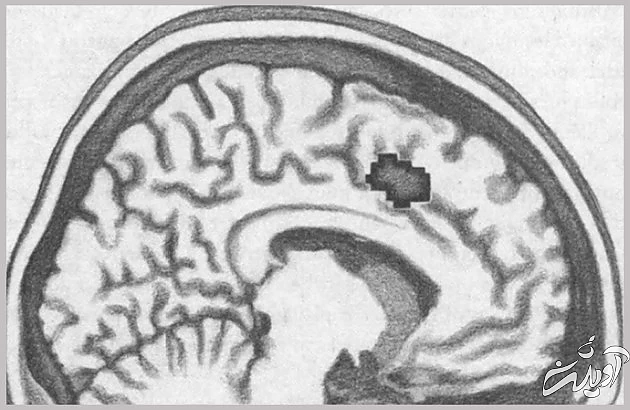

این ایده، که تنهایی را به درد اجتماعی مرتبط میکند، از استعاره فراتر میرود. تصویرسازی تشدید مغناطیس کارکردی (افامآرآی) نشان میدهد قسمت مربوط به عواطف مغز، که هنگام طرد شدن فعال میشود، سینگولیت قدامی فوقانی۸، همانی است که واکنشهای حسی به درد جسمانی را ثبت میکند.

بعد از کشف اینکه هنگام احساس طرد اجتماعی (انزوا) و واکنش در برابر درد جسمی، افزار واحدی در مغزمان به کار میافتد، رفتهرفته درک میکنیم که چرا نمیتوان صرفاً با «بیرونآمدن از حصار خود»، کمکردن وزن، تغییر ظاهر طبق مد روز یا آشناشدن با آقا یا خانمی مناسب، از دست تنهایی مزمن خلاص شد. درد و رنج تنهایی زخمی است که میتواند به اختلالات عمیقی دامن بزند. این اختلالات، که هم فیزیولوژیکاند و هم رفتاری، قادرند نیاز برآورده نشدۀ ارتباط با دیگران را به ناخوشی مزمن تبدیل کنند و اگر چنین وضعیتی پیش بیاید، برای بهبود بخشیدن به اوضاع، باید ژرفا و پیچیدگی کاملِ نقش تنهایی در زیست و تاریخ تکامل انسان را در نظر بگیریم. اگر راه کیتی بیشاپ را در پیش بگیریم و بکوشیم با خوراکیهای چرب و بازگشت به جمع رفقا حالمان را بهتر کنیم، فقط باعث بدتر شدن اوضاع خواهیم شد.

منطقهای از مغز که به درد جسمانی واکنش نشان میدهد.